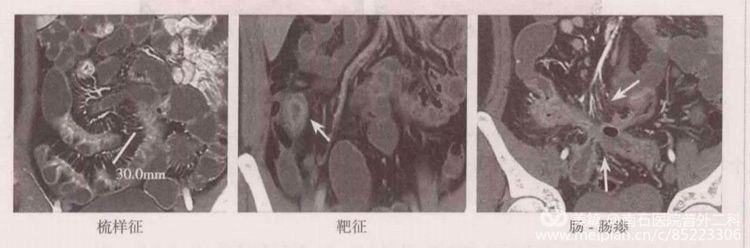

3) CTE或MRE是迄今評(píng)估小腸炎性病變的標(biāo)準(zhǔn)影像學(xué)檢查,可反映腸壁的炎癥改變、病變分布的部位和范圍、狹窄的存在及其可能的性質(zhì)(炎癥活動(dòng)性或纖維性狹窄)、腸腔外并發(fā)癥,如瘺管形成、腹腔膿腫或蜂窩織炎等。典型CD的CTE或MRE表現(xiàn)。